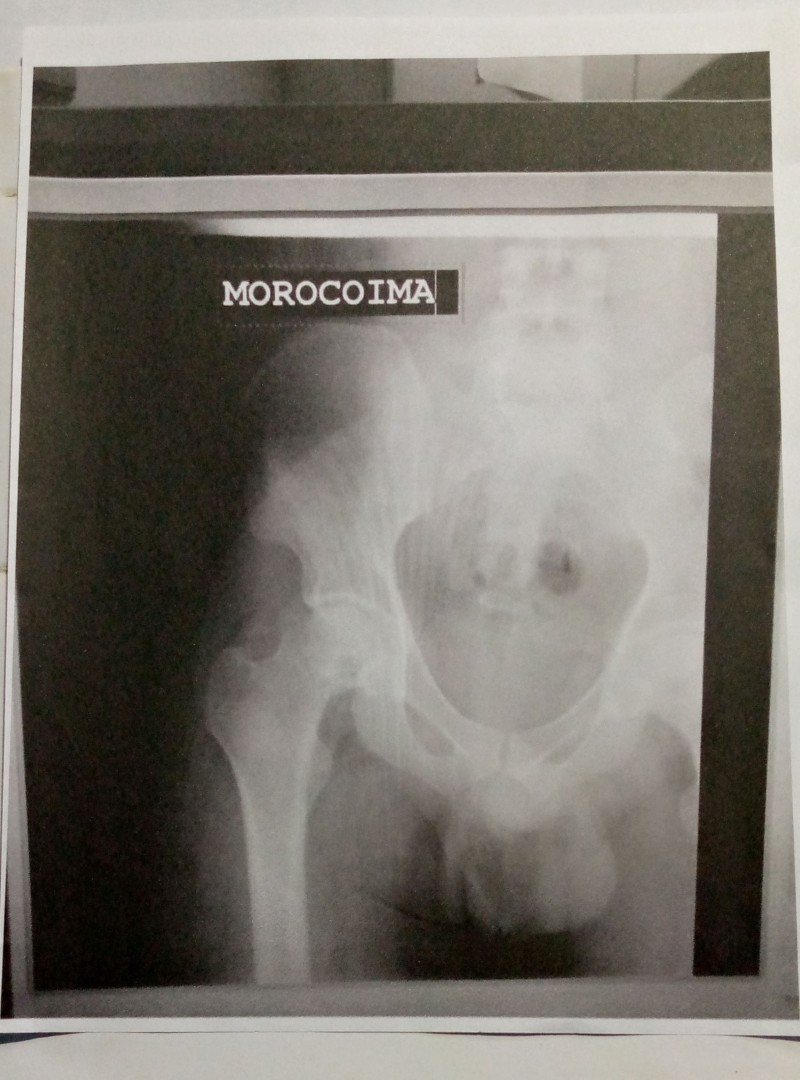

Un cordial saludo de parte de jorvin Morocoima venezolano 29 años me dirijo a ustedes para solicitar una ayuda de suma importancia me diagnosticaron necrosis vascular cadera bilateral debo ser operado requiero prótesis total d cadera no cementada ceramica polietileno de doble movilidad estos material tiene un costo de 4400$ y soy de escasos recursos económicos x tal motivo acudo confiando en su solidaridad q mi Dios me los bendiga sin más agregar mi agradecimiento de antemano su colaboración atentamente jorvin Morocoima